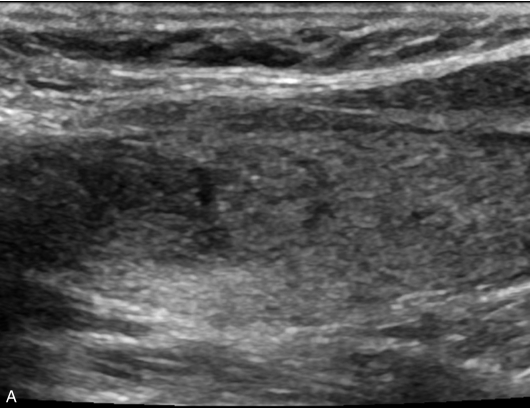

女性,56岁,体检超声发现甲状腺结节1周,无不适。甲状腺功能正常,实验室检查:FT3 3.76pmol/L,FT4 11.68pmol/L,TSH 2.8414μIU/ml。手术病理提示结节性甲状腺肿。

甲状腺形态基本正常,甲状腺实质回声稍增粗,分布尚均匀,甲状腺包膜尚光滑。甲状腺两叶内见多发结节,较大者位于左叶上极,呈类椭圆形,边界清楚,形态规则,纵横比<1,内部回声均匀,未见钙化,后方回声稍增强。CDFI显示左叶较大结节边缘可见丰富的条状血流信号,内部可见条状、点状血流信号,见图1-3-7。

图1-3-7 结节性甲状腺肿常规超声表现

A.常规超声图像;B.CDFI超声图像

甲状腺左叶上极较大结节增强早期呈稍高增强,自结节外周向中央灌注,增强晚期呈等增强,结节内部可见不均匀低增强区,见图1-3-8、ER1-3-4。

图1-3-8 结节性甲状腺肿超声造影图像